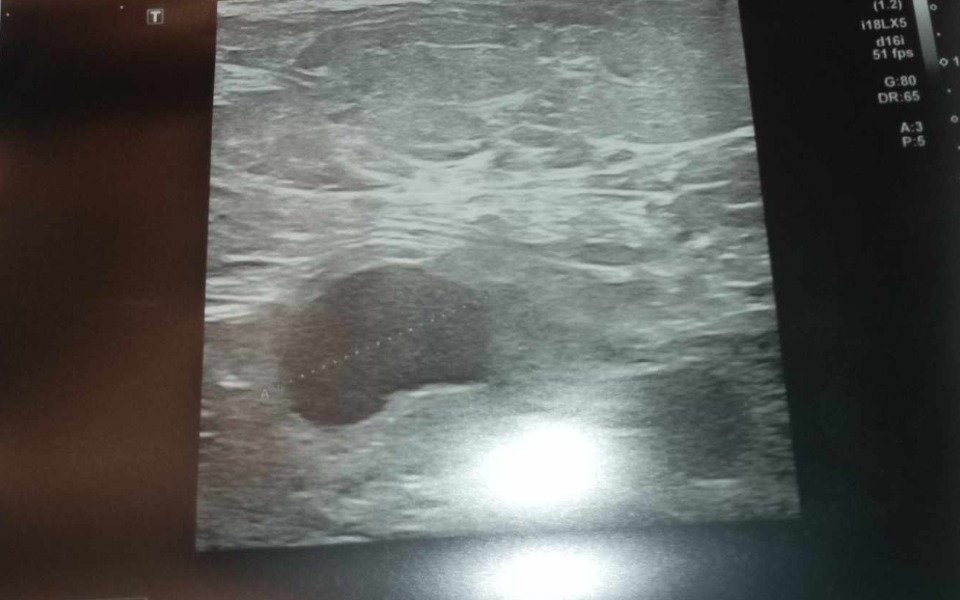

20 lutego mama usłyszała diagnozę że ma nowotwór złośliwy o piersi prawej z przerzutami do prawej jamy pachowej .Był to dla nas szok .22 lutego mój ojciec uciekł do kochanki , mam nadzieję że karma do nich wróci bo ta pani wiedziała że mama choruje na raka mimo to zrobili nam największe świństwo jakie jest możliwe .zostawiając załamana mamę i mnie . Myślałam że już nic nas nie zaskoczy ,ale 6 marca odbyło się konsylium lekarskie na którym mama dowiedziała się że nowotwór przekształcił się w zapalny i są nowe przerzuty do prawej okolicy nadobojczykowej .

ZDJĘCIA 👇👇👇👇